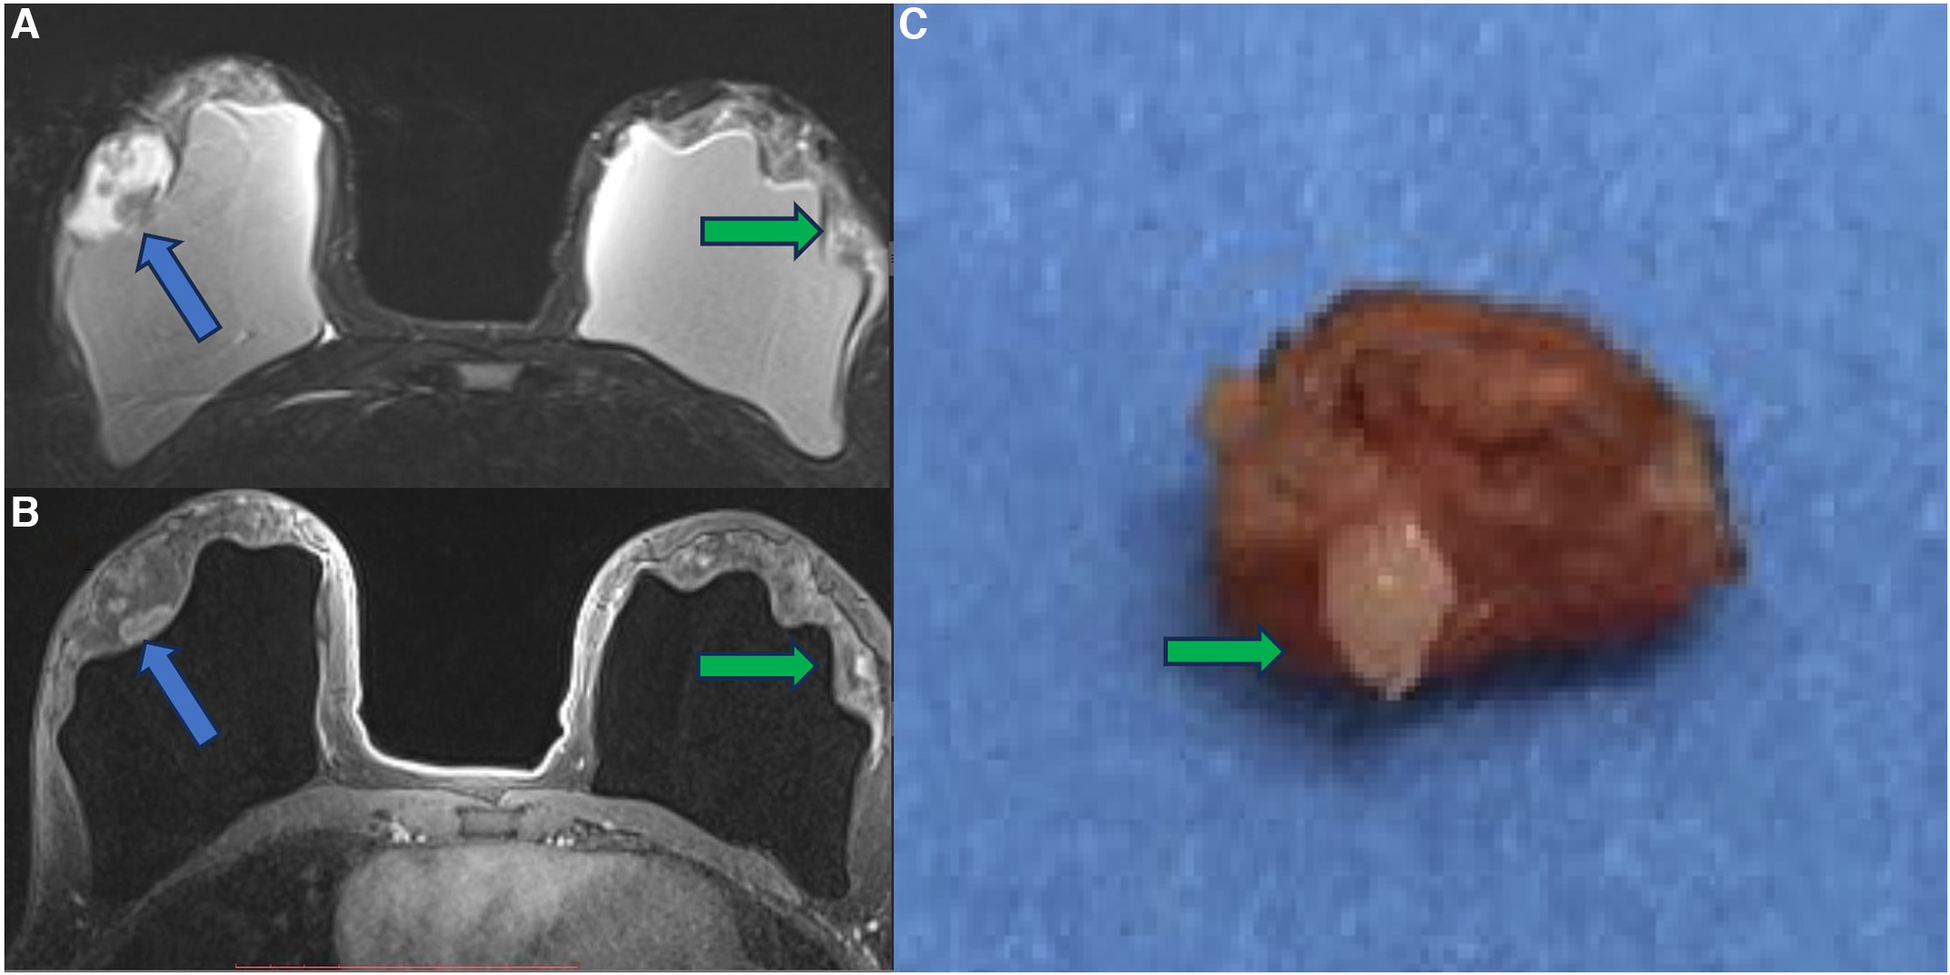

In a case report, we show a patient with a papillary breast lesion developed in the implant shell discontinuity area, where there was direct exposure of the silicone to the breast tissue. This case report corroborated our theory that the chronic inflammatory process of breast implants and silicone particle toxicity could be a triggering factor for metaplasia/dysplasia, ranging from polyclonal benign cells to monoclonal undifferentiated carcinomas (31) (Figures 10–12).

Figure 10. A 41-year-old woman with esthetic breast augmentation with silicone for six years, presenting a mass in the right breast. The axial T2** sequence (A) and axial post-contrast (B) show a histologically confirmed papilloma in the right breast (blue arrow) and a focal non-mass enhancement on the left breast (green arrow). The specimen of the left breast shows a granuloma with silicone cohesive gel content (green arrow). The imaging integrity of the silicone implants and SIGBIC findings in the left breast MRI imaging are also noted (yellow arrow).